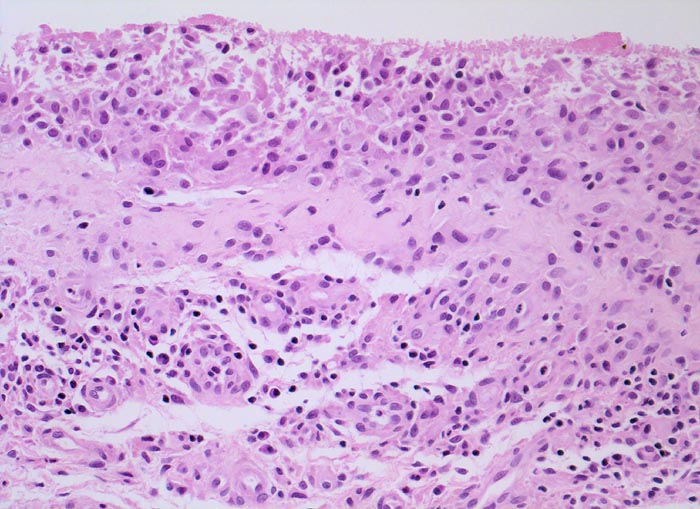

Synovialitis bei chronischer Polyarthritis

Proliferierte Deckzellschicht mit spärlichen Fibrinauflagerungen. Lockeres mononukleäres Entzündungsinfiltrat im Stroma mit Beteiligung von Plasmazellen und Histiozyten.

Bekannte seropositive chronische Polyarthritis.

Die normale synoviale Deckzellschicht umfasst 1 bis 4 Zellagen. Es handelt sich dabei nicht um epitheliale Zellen, sondern um Zellen mit Fähigkeit zur Phagozytose bzw. zur Bildung der Gelenkflüssigkeit (=Synovia).